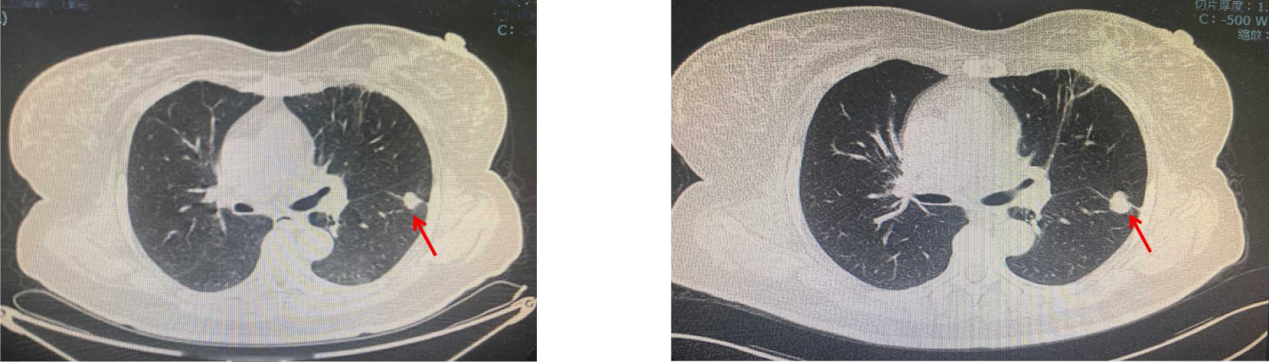

疾病进展:2020年6月,颈、胸部CT显示,双肺多发结节,考虑转移;上腹部强化MRI显示未见明显变化。

疾病进展:2021年1月,颈、胸部CT显示,双肺部分结节较前略增大。基因检测:伴PIK3CA突变。

疾病进展:2021年7月,颈、胸部CT显示,双肺多发结节较前略增大。

2022年7月复查疾病进展,双肺出现新发病灶。